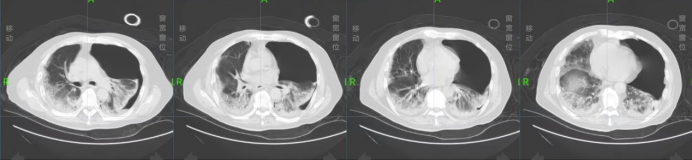

胸部CT提示:两下肺胸膜下磨玻璃影、絮片影,考虑社区获得性肺炎,病毒性肺炎?(图1)

图1  2022年11月16日胸部CT